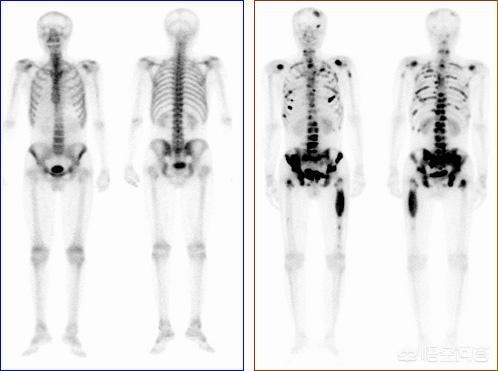

Pour les patients sans antécédents de cancer, et si la famille est financièrement aisée, il est recommandé de réaliser un examen PET-CT pour rechercher des lésions cancéreuses suspectes sur l'ensemble du corps, ce qui permet de déterminer de manière adéquate la présence de lésions tumorales, leur degré d'évolution et le type de foyers métastatiques qu'elles présentent.

En cas d'antécédents de cancer et si le degré de malignité est jugé élevé à l'époque, il est possible de déterminer la présence de métastases osseuses par une scintigraphie osseuse du corps entier. Parallèlement, le degré de destruction osseuse au niveau du site de la métastase peut être clarifié par un examen par résonance magnétique.

Par exemple, si vous êtes atteint d'un cancer du poumon et que vous ressentez depuis un certain temps une douleur persistante dans la poitrine et le dos, qui tend à s'aggraver, vous devez être attentif à la possibilité de métastases osseuses. À ce moment-là, il est nécessaire de faire un scanner pour voir s'il y a un problème au niveau de l'os. S'il n'y a pas de problème au scanner, on ne peut pas exclure qu'il n'y ait pas de métastases. Étant donné que les métastases osseuses ne peuvent pas être détectées au début du scanner, l'ECT ou la PETCT permettent de détecter les lésions de métastases osseuses à l'avance, soit 2 à 3 mois plus tôt que la détection conventionnelle des métastases osseuses.

La douleur est le premier symptôme de la plupart des métastases osseuses, >80%, et certaines métastases se manifestent à un très jeune âge. La scintigraphie osseuse (ECT) peut être pratiquée en cas de cancer du sein avec suspicion de métastases osseuses (douleur osseuse, fracture, élévation des phosphatases alcalines, hypercalcémie, etc. Certaines études ont montré que la TEP/TDM a une sensibilité similaire et une spécificité supérieure à celle de l'ECT et qu'elle peut être utilisée pour suivre l'évolution de la maladie après le traitement des métastases osseuses du cancer du sein. Si le diagnostic est difficile, un morceau d'os peut être prélevé pour un examen pathologique si nécessaire.

Les radiographies montrant une destruction osseuse ostéolytique, ostéogénique et mixte doivent également être envisagées pour détecter un éventuel cancer osseux métastatique. La scintigraphie osseuse est une méthode sensible pour détecter les tumeurs osseuses métastatiques.

Les métastases osseuses désignent l'implantation de cellules tumorales d'autres parties du corps dans le périoste pour former un cancer, également appelé cancer secondaire avec métastases osseuses. À l'heure actuelle, on constate que le cancer du rein, le cancer du pancréas, le cancer du rectum, le cancer de l'estomac, le cancer de la thyroïde, le cancer du poumon, le cancer de la prostate parmi les tumeurs masculines, le cancer du sein et le cancer de l'ovaire parmi les tumeurs féminines sont prédisposés aux métastases osseuses. Par conséquent, si l'un des cancers susmentionnés survient, nous devrions être attentifs aux métastases osseuses et subir des examens réguliers si nécessaire.scintigraphie osseuseet d'autres contrôles.